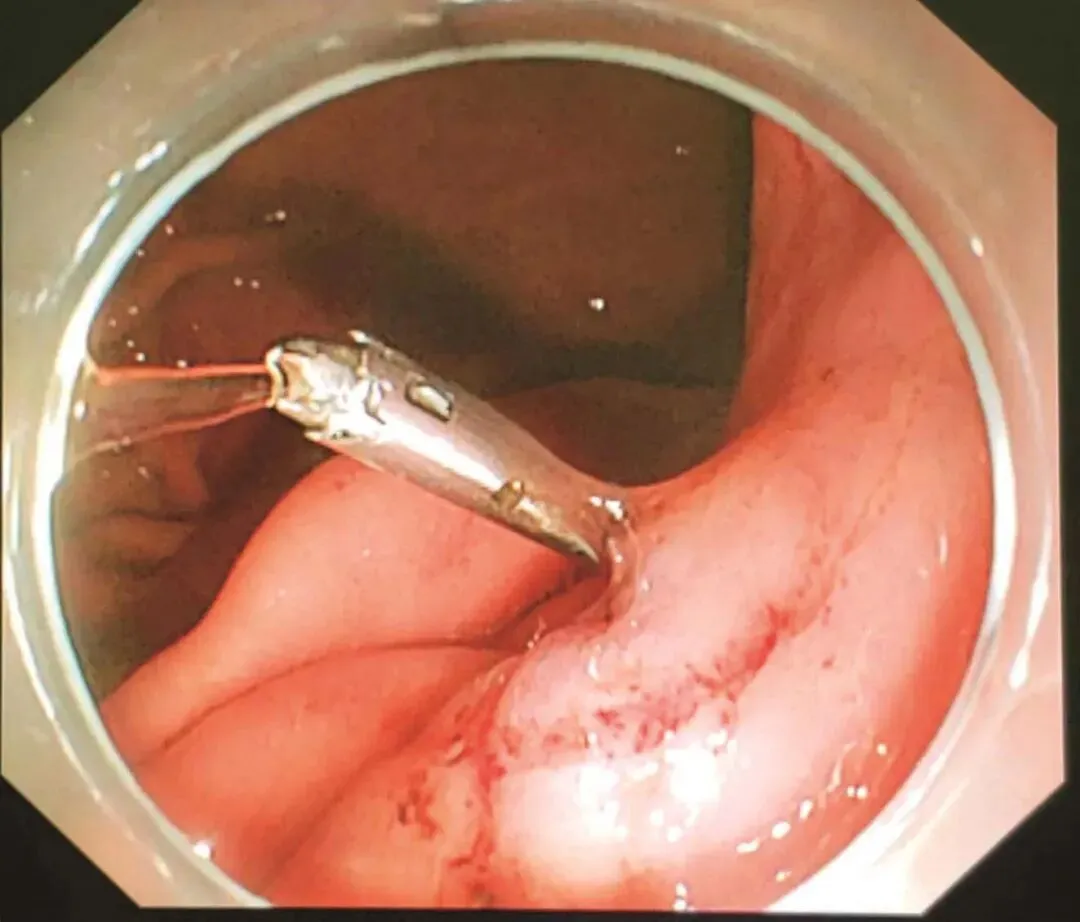

患者于2018年08月30日在笔者单位接受“腹腔镜+胃镜双镜联合胃肿瘤切除术”,胃肠外科与消化科医师共同上台。术中内镜见胃体小弯侧后壁直径4cm黏膜下肿瘤,腔内生长,未侵犯胃黏膜及浆膜(图2-3),胃周淋巴结无肿大,小网膜囊内可及直径1cm钙化脂肪结节一枚,肝脏、盆腔、腹膜未及转移灶。经口置入内镜,探查肿瘤,于肿瘤边缘黏膜下注水(图2-4);内镜指引下,腹腔镜下以超声刀距肿瘤边缘1cm切开胃壁浆膜,沿肿瘤包膜外,全层切开胃壁,完整切除肿瘤(图2-5);以3-0可吸收线间断全层缝合胃壁缺损;术中胃镜检查胃创面;创面部分黏膜缺损处内镜下以钛夹封闭(图2-6);肿瘤标本置于标本袋内,经脐部戳孔处取出(图2-7)

图2-5 术中内镜监视下由外科医师完成腹腔镜下肿瘤切除